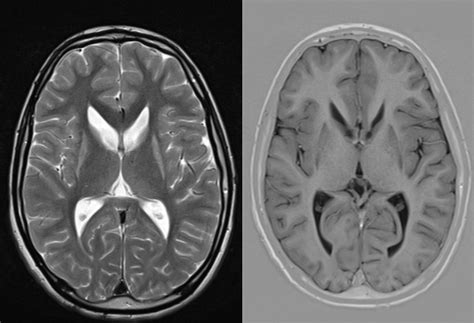

One of the really tragic aspects of the Huntington’s disease pathway is that not all neurons are equally affected. While HD is a global brain disease, certain brain regions and specific types of neurons are much more vulnerable than others. This selective vulnerability helps explain the characteristic symptoms of the disease. The striatum , a part of the basal ganglia crucial for motor control, cognition, and emotion, is particularly hard-hit. Within the striatum, medium spiny neurons (MSNs) are especially susceptible to the toxic effects of mHTT. These neurons use the neurotransmitter GABA and play a critical role in modulating movement and behavior. As these MSNs degenerate, it leads to the characteristic motor symptoms of HD, like chorea (involuntary jerky movements) and rigidity. But it’s not just the striatum. Other brain areas, including the cerebral cortex (involved in thinking, planning, and memory) and the hippocampus (critical for learning and memory), also experience neuronal loss. This explains the cognitive decline and memory problems seen in HD patients. The reasons for this selective vulnerability are still being investigated, but it’s thought to involve a combination of factors. For instance, MSNs might have a higher baseline level of oxidative stress, making them more susceptible to damage from the free radicals produced by mitochondrial dysfunction. They might also have specific metabolic needs or rely heavily on certain cellular pathways that are particularly sensitive to mHTT toxicity. The differential expression of genes and proteins in these vulnerable neurons could also play a role. This targeted destruction of specific neuronal populations is what gives Huntington’s disease its distinct and devastating clinical profile. It’s not random destruction; it’s a targeted assault that cripples specific brain functions.